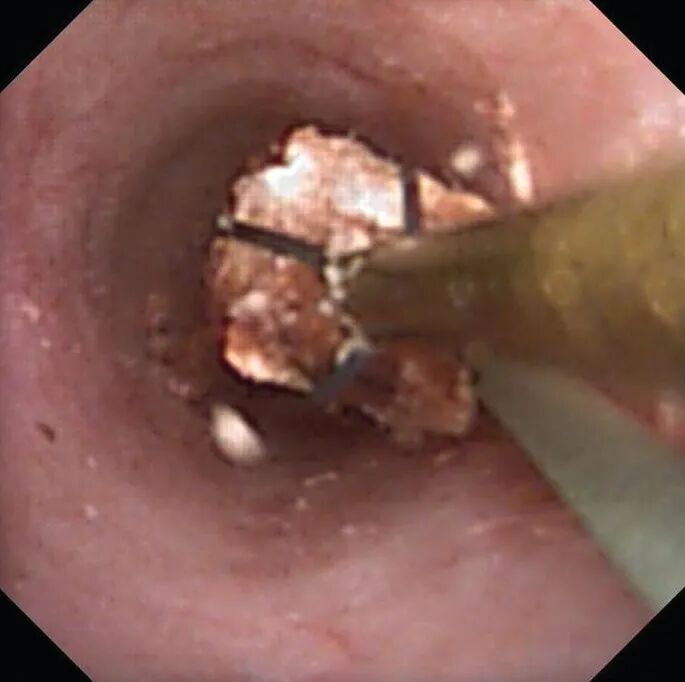

上尿路肿瘤活检和消融。

软镜已被用于治疗肾盂旁囊肿、肾盏憩室和输尿管 / PUJ 狭窄。一旦 F-URS 进入肾盂,囊肿就被识别出来,并用激光切开和引流肾囊肿壁。将切开后的输尿管支架置入囊肿并在 4 周后取出。对于憩室,在超声或透视引导下注射亚甲基蓝以识别憩室颈。集合系统用生理盐水冲洗后,内窥镜下可以看到憩室漏出的染料,然后用激光切开憩室颈部。对于输尿管狭窄,需要定位并进行全层切口。为避免血管损伤,近端狭窄在后外侧进行,远端狭窄在前内侧进行。